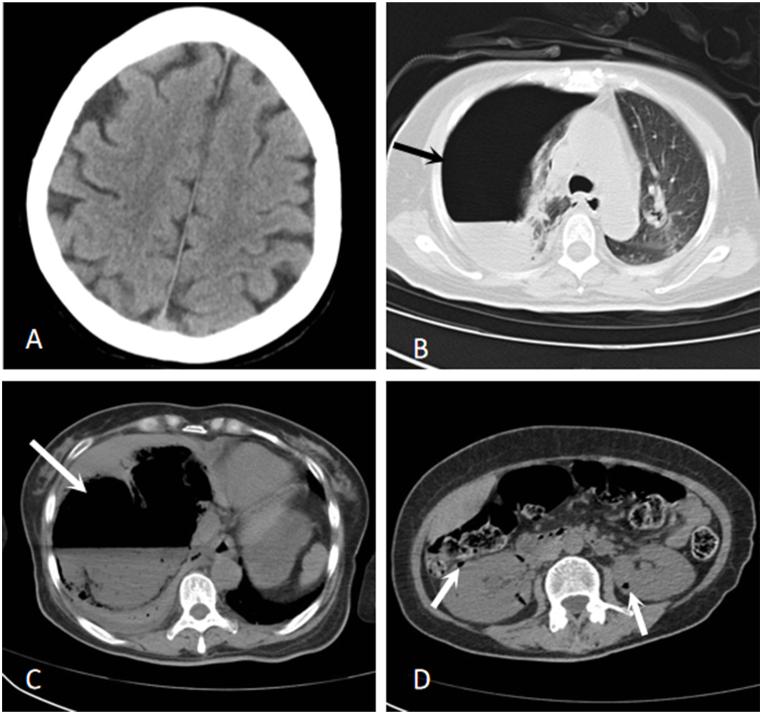

A 54-year-old female with diabetes was admitted with fever and altered consciousness. Laboratory tests revealed venous blood glucose level of 43.79 mmol/L. Computed tomography (CT) scans of the head, chest, and abdomen showed a right-sided pneumothorax, consolidation, and atelectasis in the right lung; a large heterogeneous density lesion with fluid and gas-fluid levels in the liver; and scattered gas shadows in both kidneys, respectively. Blood and puncture fluid cultures indicated infection with . Based on the susceptibility profiles of the isolates, imipenem was administered intravenously to treat the infection. On the third day of hospitalization, the patient's condition worsened, with head CT showing an extensive cerebral infarction and multiple gas accumulations in the right cerebral hemisphere, as well as a large-area cerebral infarction in the left parietal and occipital lobes. Ultimately, the patient died of multiple organ dysfunction on the fourth day after initial presentation. Although the isolates from the patient showed sensitivity to imipenem, this antibiotic shows poor entry into the central nervous system. The death of the patient indicates that the selection of antibiotics that can cross the blood-brain barrier may be crucial in the outcome of this type of case. Therefore, antibiotics that can penetrate the blood-brain barrier should be selected as soon as possible, and empirical treatment must be initiated immediately after clinical suspicion of invasive , even if the diagnosis has not been determined.